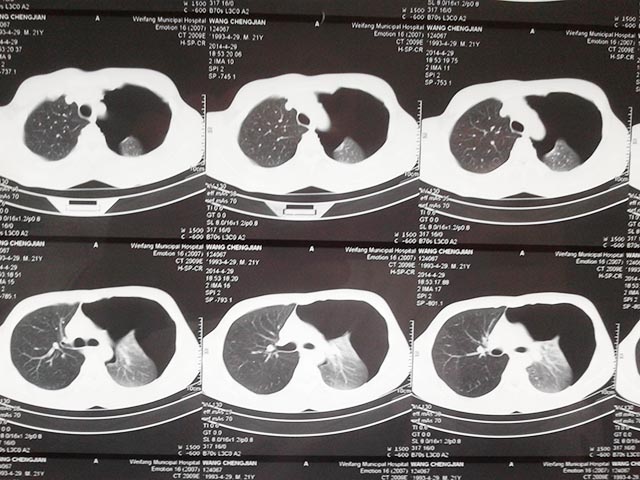

隨即做了胸部CT檢查,發(fā)現(xiàn)左側(cè)肺組織已經(jīng)壓縮了50%,并且雙肺可見多發(fā)彌漫的肺大皰,在與患者及家屬溝通后,先行左側(cè)胸腔閉式引流術(shù),排出了積氣,緩解了癥狀,穩(wěn)定了生命體征。

在第二天查房時(shí)胸外科楊新峰主任詳細(xì)詢問(wèn)老王的病情,分析患者為繼發(fā)于慢性阻塞性肺氣腫的肺大皰破裂導(dǎo)致的氣胸,需要行左肺大皰切除+胸膜固定術(shù)手術(shù)治療。但這個(gè)病人比較特殊,雙肺的肺大皰,如果使用雙腔管,術(shù)中單肺通氣,手術(shù)操作方便,但是既要保證充足氧氣供應(yīng),又要避免對(duì)側(cè)肺大泡破裂,是個(gè)難題。為制定科學(xué)的手術(shù)方案,經(jīng)胸外科、麻醉科專家會(huì)診,決定使用單腔管,在低潮氣量,高頻雙肺通氣下進(jìn)行手術(shù)。